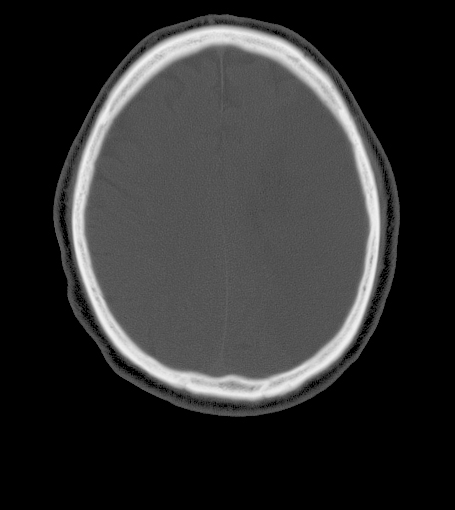

Head and Neck Radiology CT Cranial Vault

Frontal Bone

Occipital Bone

Parietal Bone